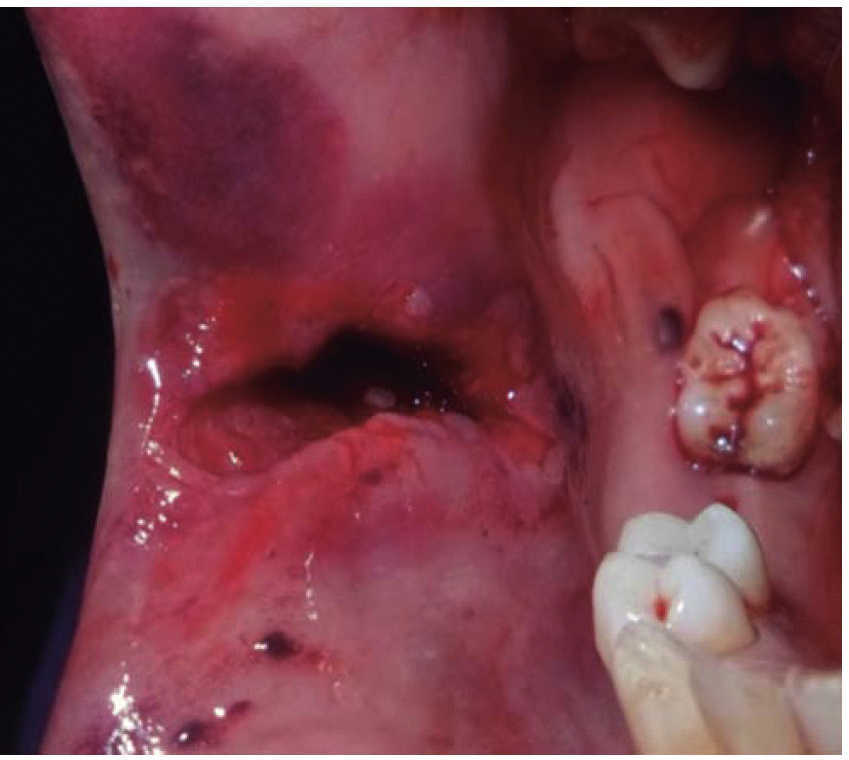

The first case was that of a 30 year old male, with diagnosis of fracture of left mandibular body caused by firearm. The patient was assaulted after a fight which took place when he was leaving a nightclub, he received a bullet shot at a 4 meter distance. Patient exploration revealed edema at cervical, middle third and lower facial levels; he exhibited entry orifice at the left genial region and exit wound at the right submandibular level (Figure 4). Intraoral examination revealed a wound in the mandibular alveolar process at the fracture line, and absence of teeth (Figure 5). Treatment was initiated under general anesthesia with airway stabilization provided by tracheotomy. Debridement of wound edges was performed locally, with surgical soap washes, physiological solution and wound suture. After soft tissue treatment was completed, initial occlusal stability was attempted with an Erich-type bar arch. The patient was hospitalized under a therapeutic scheme of immunization, antibiotics and analgesics.

A 48 year old male arrived for treatment with diagnosis of facial wound caused by firearm. He was assaulted by a third party in the street. He did not inform of the shooting distance. The patient exhibited a projectile entry wound at the right genial region and no exit wound (Figure 8). Intra oral examination revealed a wound in the right cheek, tooth fracture at the level of the upper right hemi-arch, with fractures at the dental neck of first and second premolars and first molar (Figures 9 and 10) involvement. Under local anesthesia, the wound was washed with surgical soap and abundant physiological solution. The tongue was superficially dissected, the bullet was extracted (Figure 11), hemostasis was performed and wounds were sutured. Tooth remains were considered rests and deemed unable to be restored, for that reason they were extracted. The patient attended periodic evaluations with suitable healing of soft tissues and alveolar process. The patient refused implant therapy due to financial considerations, he was thus referred to be rehabilitated with a removable prosthesis.

A 73 year old female with diagnosis of fracture of left mandibular body due to firearm projectile (Figure 12). The patient informed she was assaulted in the street, and upon offering resistance to the theft of her vehicle, she was shot at a distance of two meters. She arrived at our institution eigt days after the assault, having previously been treated in another hospital. Physical exploration revealed hyperemic area and volume increase in fluctuating left submandibular region; entry orifice at left submandibular level with presence of fetid whitish secretion and closed exit wound at right cervical level. Intraoral examination revealed partial edentulism, with multiple maxillary septic foci, and at the left mandibular fornix, a root remnant of the first molar in the fracture line as well as accentuated mobility of the mandibular segment caused by fracture which hindered deglutition.